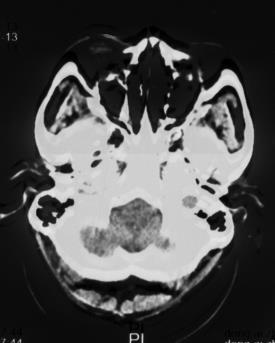

复阅2018年5月9日CT片:右枕顶部软组织肿胀、密度增高,右枕骨见线状骨质断裂、骨折线累及斜坡,右枕部颅板下见梭形致密阴影,大脑镰旁见线状致密阴影,左额颞部颅板下见弧形致密阴影,右额叶及左额颞叶均见斑片状高低混杂密度影,尤以左额叶明显,右侧小脑见斑片状高低混杂密度影。提示右枕顶部头皮血肿,右枕骨骨折,右枕部硬膜外血肿,蛛网膜下腔出血,右颞部硬膜下血肿,右额叶及左侧额颞叶脑挫裂伤,右侧小脑挫裂伤。

图1-5,2018年5月9日 CT片,右枕顶部头皮血肿,右枕骨骨折,右枕部硬膜外血肿,蛛网膜下腔出血,右颞部硬膜下血肿,右额叶及左侧额颞叶脑挫裂伤,右侧小脑挫裂伤